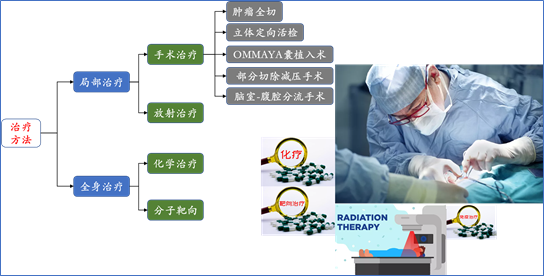

肝癌脑转移强调个体化综合治疗,需要在病理诊断及分子病理特点基础上,依据病人具体情况,制定最适合该病人的最佳方案。主要包括以下几种:

神经外科手术

手术方法主要包括:开颅肿瘤切除术、Ommaya囊植入术、神经导航下颅内病灶活检术、脑室-腹腔分流术等。

放射治疗

主要适用于:多发或者单发脑转移病灶、手术切除肿瘤后的辅助治疗等。

主要方法包括:立体定向放疗(SRS)、全脑放疗(WBRT)等。

其它治疗方案

主要包括:针对肝癌原发及脑转移灶的全身化疗、分子靶向治疗、免疫治疗等。